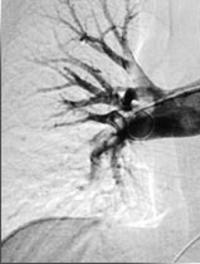

Les piqûres de méduses peuvent entraîner des lésions cutanées minimes et transitoires mais aussi, selon les espèces, des réactions cutanées majeures et des conséquences systémiques qui peuvent, dans les cas les plus sévères, être fatales. À l’heure des vacances et des voyages lointains, connaître les problématiques liées aux piqûres de méduses selon les régions du monde est nécessaire. Un homme de 45 ans, sans problème de santé, consultait pour des lésions très douloureuses, [...]